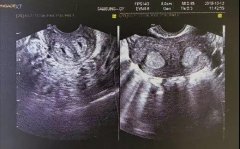

胎儿心脏彩超丨探头下揭秘胎儿心脏!

先天性心脏病是一种常见的先天性发育畸形,也是导致流产、胎儿宫内死亡以及...【详情】 57 人关注